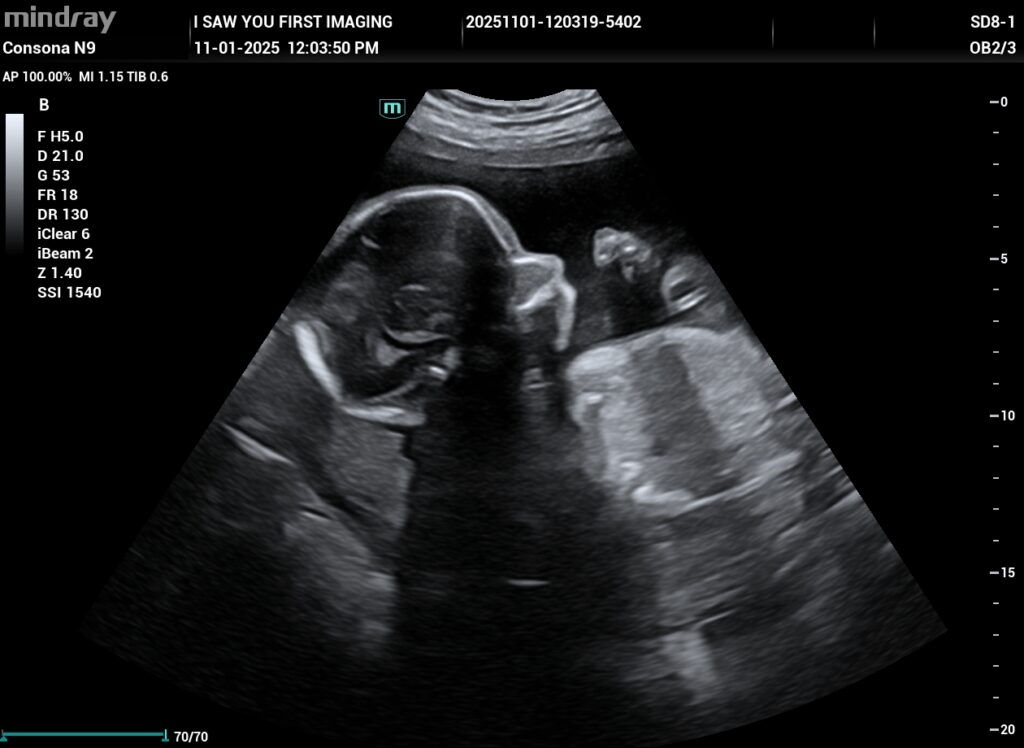

When families walk into our studio, many imagine the womb as a calm and quiet place. Then we turn on the screen. Almost every time, there is laughter. Babies are busy. They stretch, roll, kick, yawn, and sometimes even suck their thumb. When parents come to us searching for elective ultrasounds near me, they often tell us they never expected to see this much activity.

For us, these little moments are the best part of what we do. No two scans are ever the same.

One of our favorite things to catch during a scan is a baby yawning. It usually makes the whole room smile. Yawning helps babies develop their jaw muscles and get ready for feeding after birth.

Hiccups are another common sight. Babies get hiccups while practicing breathing and swallowing. With the clear imaging we use at our elective pregnancy ultrasound studio near Cherry Hill, NJ, these small movements are easy to spot. They might look funny, but they are healthy and normal.

Sometimes we even see tiny facial expressions. A brief pout. A scrunched nose. A relaxed face. These reflexes may be simple, but for parents, they feel deeply personal.